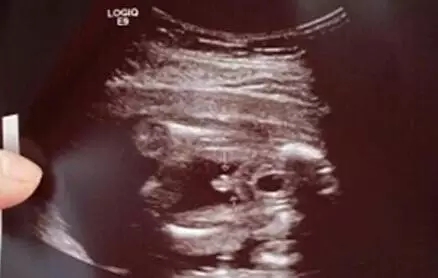

一、B超单内暗含玄机

聪明的妈妈们其实早已总结出了很多经验,最有靠谱的莫过于从B超单中查找各种蛛丝马迹然后成功推断宝宝的性别,每个成功的妈妈其强大程度不亚于破获各种大案难题的世界神探。

B超图分辨男宝女宝性器官

在照B超的时候,医生都会从屁股底下照看看左右的大腿,仔细观察的话可以发现在图中会有“谜之小凸起”,上图中的箭头所指就是,看到这里相信不用我说各位也一定看出来是一位小王子了。